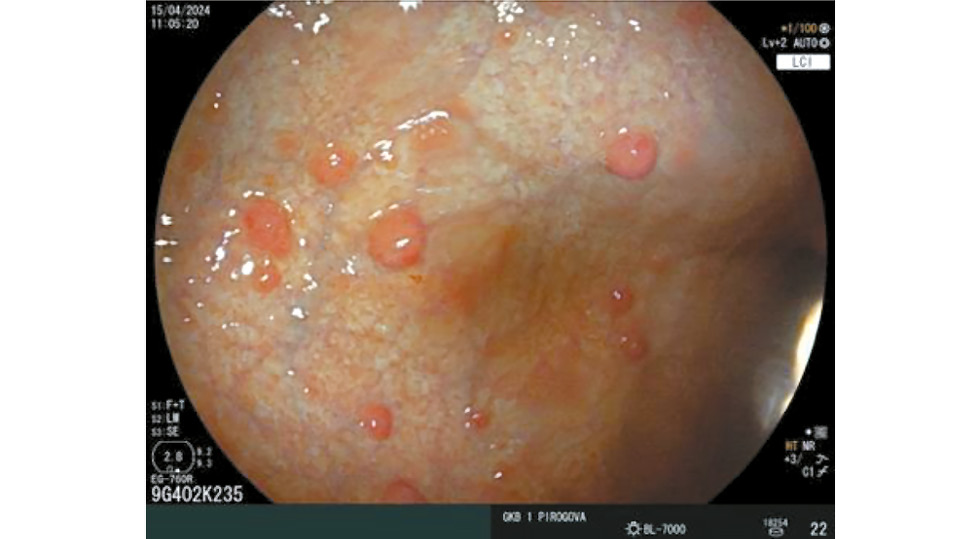

A characteristic feature of autoimmune gastritis is the presence of patches of preserved acid-producing mucosa [41]. Terao et al. described this phenomenon as pseudopolyps against the background of diffuse gastric body atrophy, observed in 31.5% of cases (Fig. 3) [27].

Fig. 3. Endoscopic view of preserved acid-producing areas of the gastric body mucosa. © Eco-Vector, 2025.

Hyperplastic polyps are common in autoimmune gastritis [17]. Arai et al. found a higher incidence of gastric cancer in patients with autoimmune gastritis and hyperplastic polyps [49]. Similarly, Zhang et al. reported that cancer risk increases in the presence of large or multiple hyperplastic polyps [50]. The prevalence of hyperplastic polyps in autoimmune gastritis is 21.2% (Fig. 9) [27].

Fig. 9. Multiple hyperplastic polyps of the gastric body in autoimmune gastritis. © Eco-Vector, 2025.